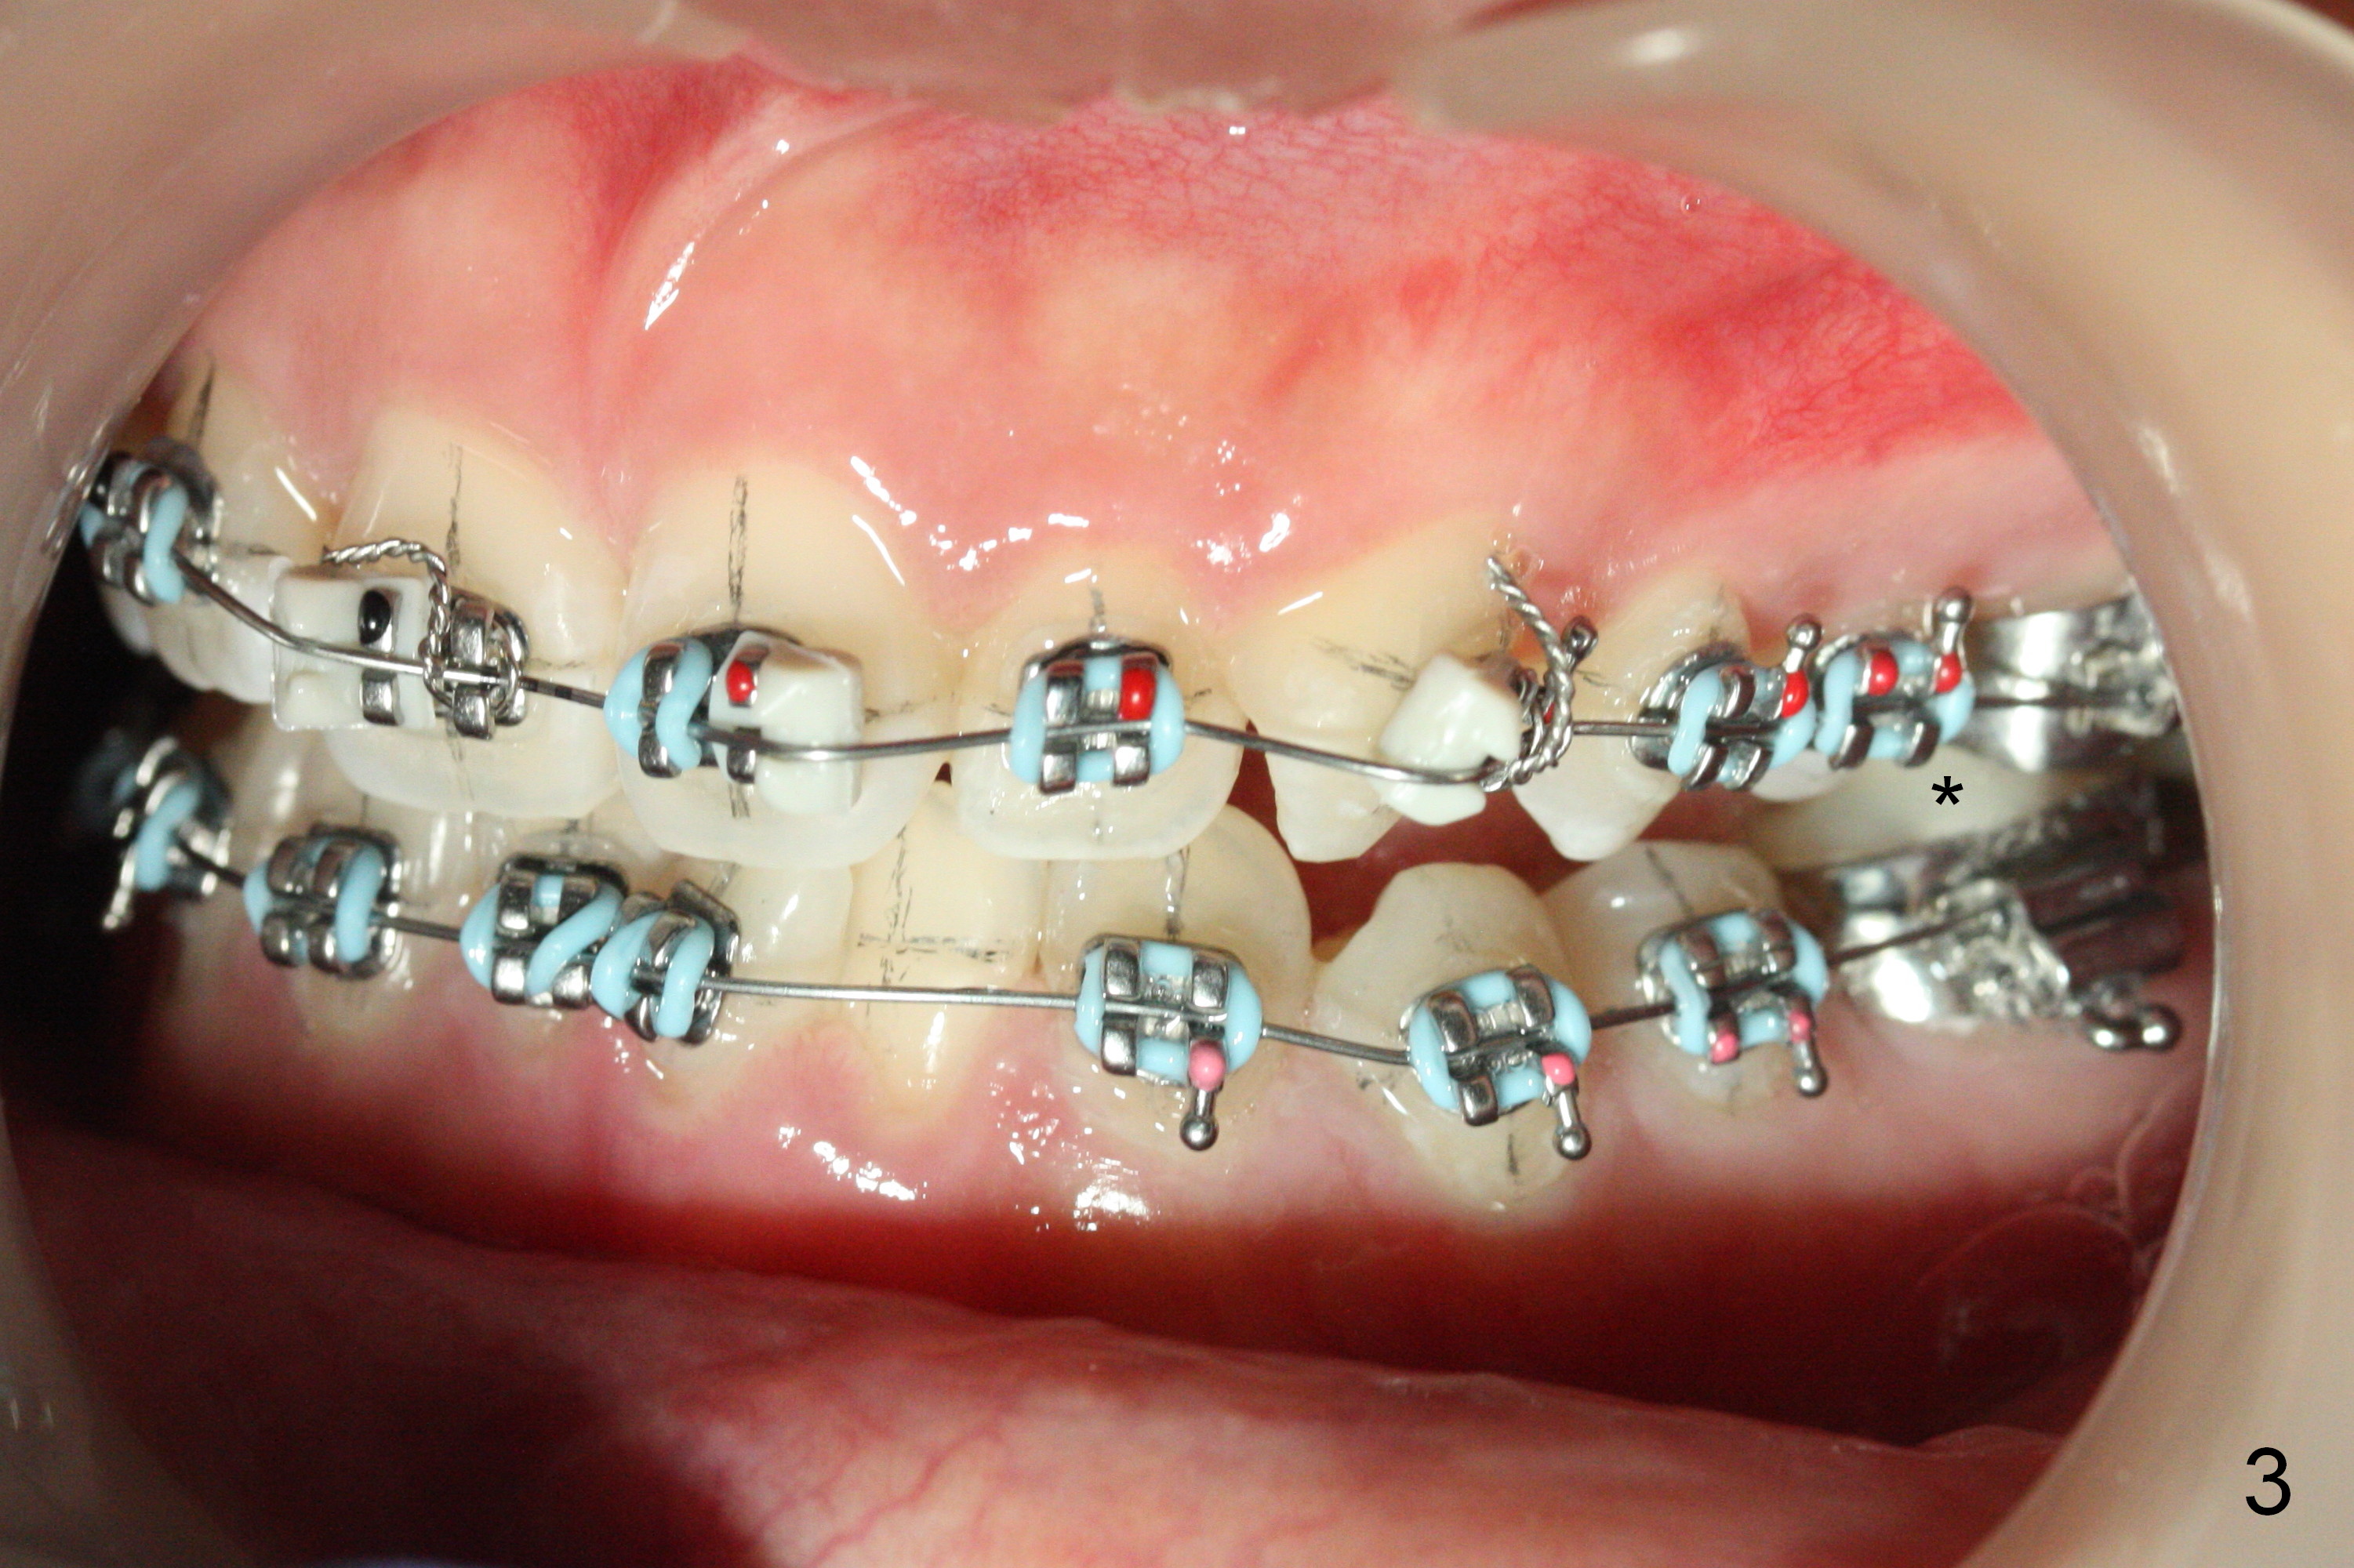

Class II Division II malocclusion is characterized by the lingual inclination of the upper anterior teeth so that there is not enough clearance to place brackets for the lower incisors (Fig.1). Composite has to be placed on the occlusal surface of the molars (Fig.3 *). The patient must have difficulty in mastication for a few days. Is there a better method to avoid the inconvenience?